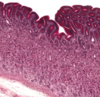

Stomach mucosa- lamina propria, gastric pit, neck, gastric gland, muscularis mucosa

Parietal (A) & Chief Cells (B) in Stomach

Fundic gland - lumina (L) of the fundic glands can be recognized. The chief cells (CC) are granular in appearance and are much smaller than the round, plate like parietal cells (PC). Parietal cells, so their name imply, are located at the periphery of the gland. Slender connective tissue elements (CT), housing blood vessels, occupy the narrow space between the closely packed glands.